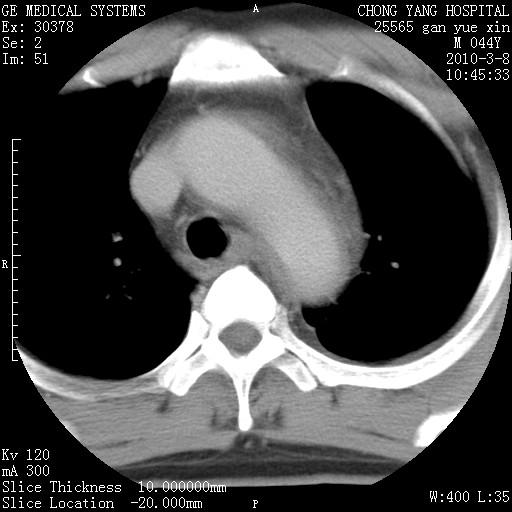

标题: CT24940:主动脉增强,典型病例。 [打印本页]

标题: CT24940:主动脉增强,典型病例。

夹层动脉瘤。

动脉夹层

夹层动脉瘤,典型

主动脉夹层。

动脉夹层的分型:

⒈debakey分型:根据主动脉夹层累及部位,分为三型:ⅰ型:原发破口位于升主动脉或主动脉弓部,夹层累及升主动脉、主动脉弓部、胸主动脉、腹主动脉大部或全部,少数可累及髂动脉。ⅱ型:原发破口位于升主动脉,夹层累及升主动脉,少数可累及部分主动脉弓。ⅲ型:原发破口位于左锁骨下动脉开口远端,根据夹层累及范围又分为ⅲa,ⅲb。ⅲa型:夹层累及胸主动脉。ⅲb型:夹层累及升主动脉、腹主动脉大部或全部。少数可累及髂动脉。

⒉stanford分型:a型:夹层累及升主动脉,无论远端范围如何。b型:夹层累及左锁骨下动脉开口以远的降主动脉。

夹层动脉瘤,少量胸水

夹层动脉瘤;左侧少量胸腔积液。

典型主动脉夹层。